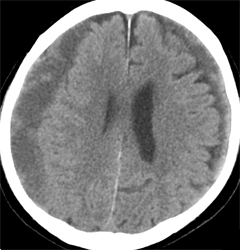

경막하 출혈의 진단은 환자의 신체검사와 함께 여러 가지 검사방법을 통해 이루어집니다.

- CT 또는 MRI 스캔 : 출혈량과 위치를 확인하기 위해 실시됩니다.